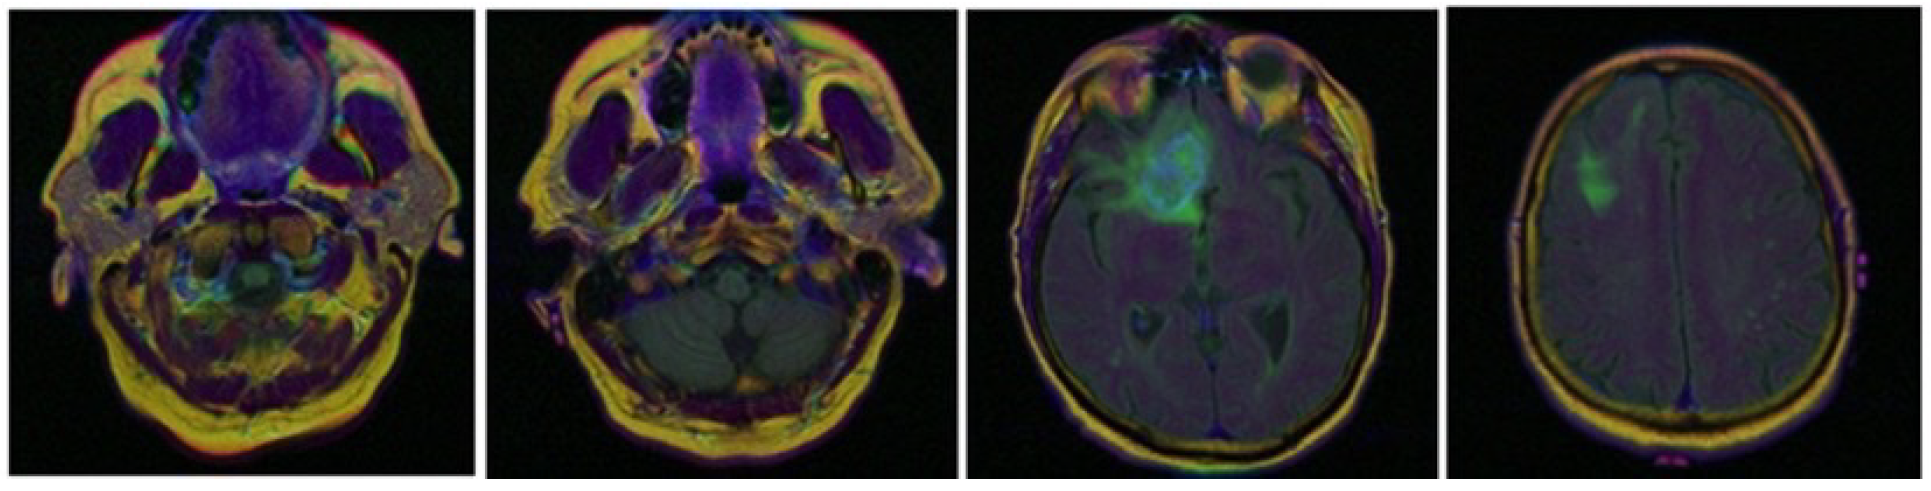

The Cancer Genome Atlas Low Grade Glioma (TCGA-LGG) dataset will be used as part of a larger effort to create a research community focused on linking cancer phenotypes to genotypes by providing clinical images matched to Cancer Genome Atlas (TCGA) subjects (Figure 4).

Regarding the classification task, we used the Gradient-weighted Class Activation Mapping (Grad-CAM) [46] method as a visual tool expressing the model’s way of thinking in the process of classification, highlighting the regions indicating the probability that the image belongs to a predefined class. As the images in Figure 9 clearly illustrate, these attention maps reflects which parts of the brain, skin, prostate or lung is getting the model’s attention most to improve its classification process.

Figure 4. Samples of Brain Tumor from TCGA-LGG dataset.

Figure 9. Grad-CAM on samples from the four Datasets.